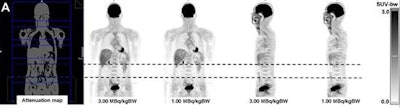

FDG-PET images show good image quality in a 43-year-old patient with a dose of 1 MBq/kgBW (A). However, there was an artifact in the abdominal region (B) at lower doses. This region was located completely within one bed position (dotted line). Images courtesy of JNM.Interestingly, the readers considered most PET images with FDG doses of 1.25 to 2.75 MBq/kgBW to be just as good as those with 2 MBq/kgBW. One PET image with 2.75 MBq/kgBW and nine PET images with 3 MBq/kgBW were rated as substantially better.

Still, the researchers encountered artifacts in PET images of the urinary bladder in three patients, as well as large photopenic areas in the middle abdomen in two different patients.